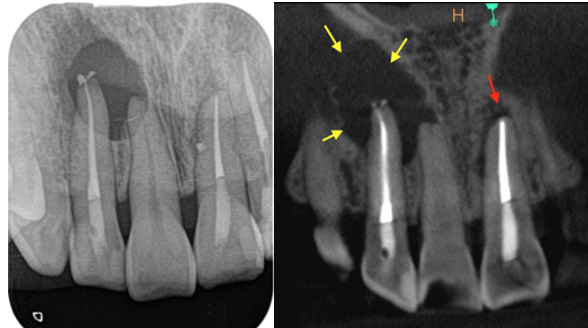

術前、右上2に大きな透過像(黄色矢印、炎症の黒い影)と左上1にも透過像(赤矢印)が見られます。腫れの原因は、歯髄壊死と根尖性歯周炎と診断し、まずは根管治療を行いました。左上1の根尖も透過像(緑矢印)がありましたが、歯髄の反応は正常でしたので歯髄壊死とは診断せず治療は行いません。

• 根管治療後4ヶ月、左上1の透過像(赤矢印、黒い影)は小さくなり治癒傾向が確認できますが、右上2(赤矢印)は以前より広がってきていて、腫脹の再発がありました。非治癒判定となり、次の治療法として歯根端切除術を行うこととなりました。歯根端切除術を行わない医院ではこの時点で抜歯が宣告されてしまうでしょう。

• 術前レントゲン画像

• 歯根端切除術後1年のレントゲン画像